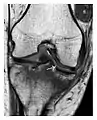

a

b

Figure 9: Proximal metaphyseal fatigue fracture of the tibia in a 27-year-old recent male military recruit. (a) Anteroposterior radiograph is within normal limits. (b) Coronal T1-weighted MR image shows a marked linear hypoattenuation along the medial tibial metaphysis (arrow) surrounded by diffuse hypointensity in keeping with posttraumatic edema.[1]